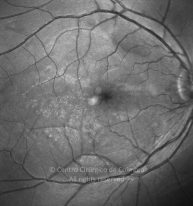

Paciente de 37 años con traumatismo contundente y ruptura del globo ocular. Presenta ruptura esclero-uveal, hifema, hemovítreo, desgarro periférico y temporal de la retina, hemorragias subretinianas y múltiples desprendimientos serosos.

MAVC: 20/25 OD, nueve años después de las cirugías (sutura escleral de la desinserción del músculo recto externo, vitrectomía posterior y fotocoagulación láser en el borde del desgarro retiniano, desprendimiento de retina inferior con proliferación vitreorretiniana y líquido subretiniano con algo de sangre; peeling de la membrana epirretiniana y maculorrexis de la MLI).